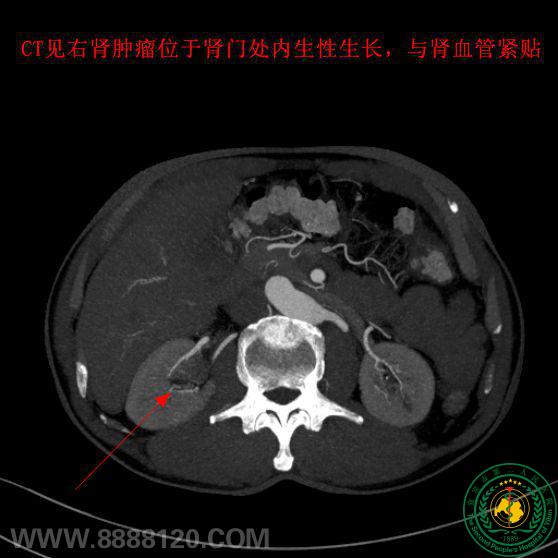

但患者右肾肿瘤为肾盂处内生性生长,并且被肾动脉及肾静脉等多个重要血管包裹,手术难度极大,风险极高。